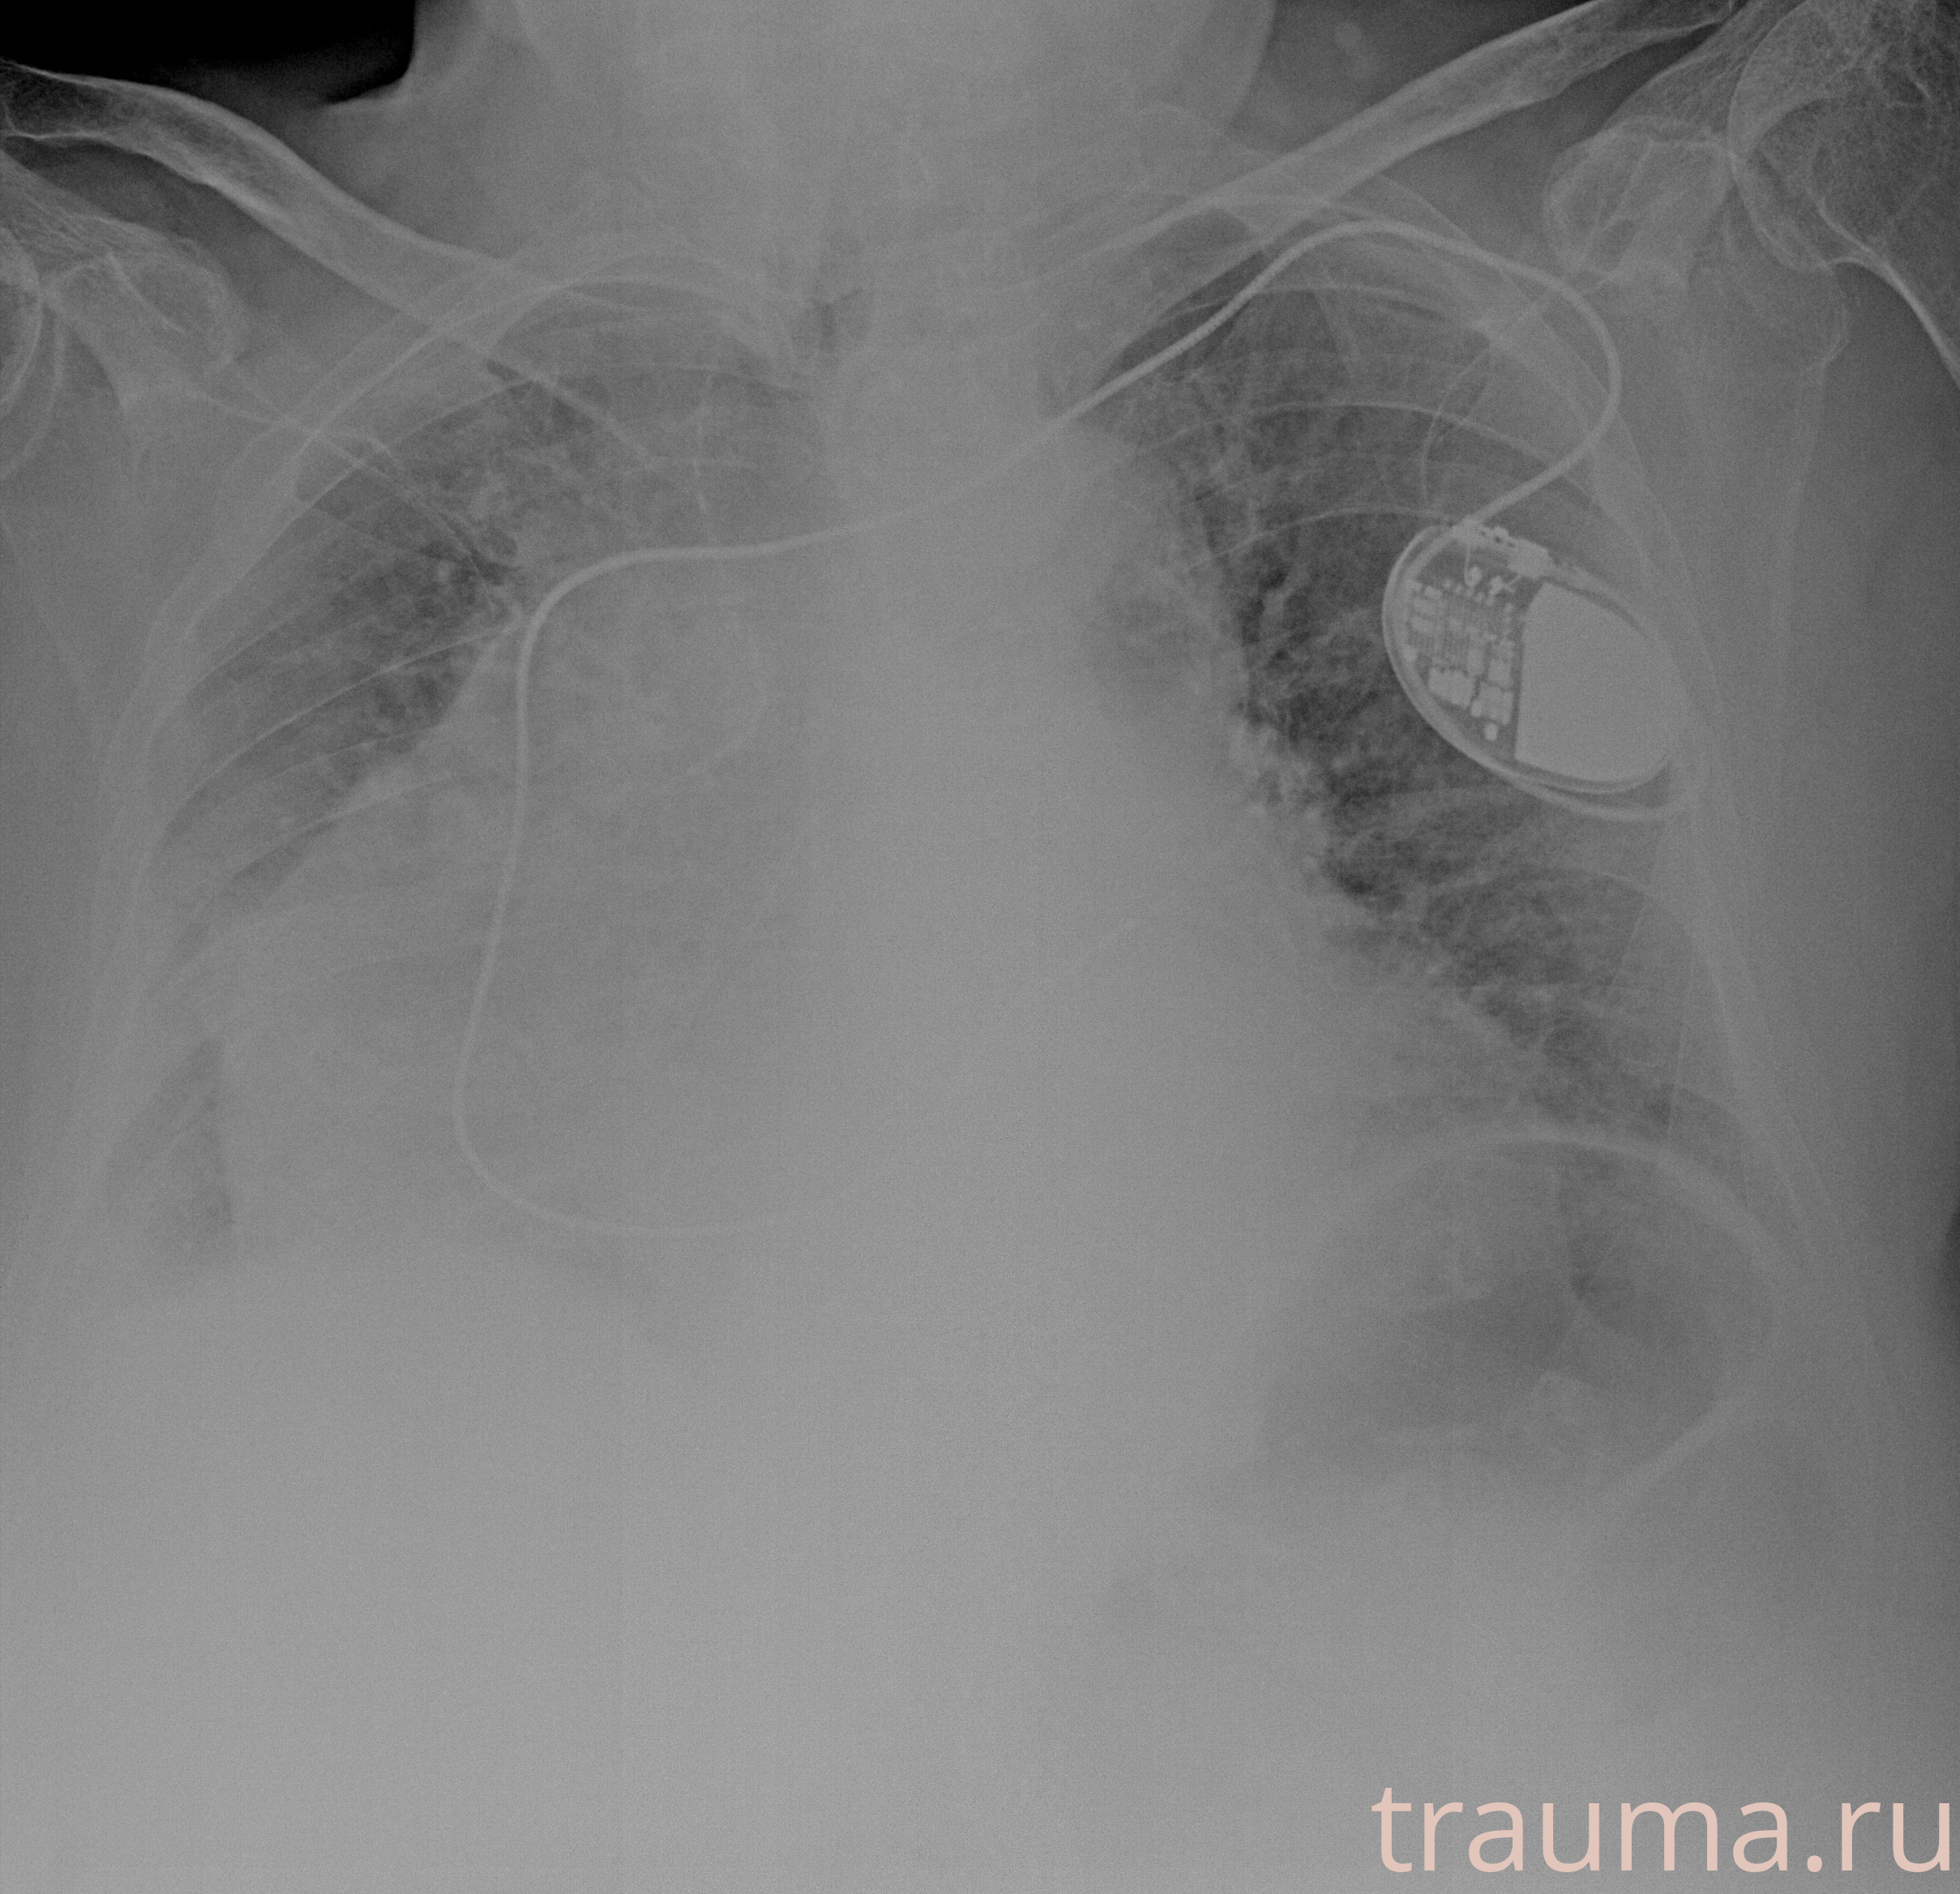

Рентген на дому: по вашему адресу приезжает врач-рентгенолог, травматолог-ортопед с мобильным рентгеновским аппаратом, проводит диагностику травмы или заболевания, делает необходимые рентгенограммы, дает рекомендации по дальнейшему лечению. Получить качественные снимки в домашних условиях возможно благодаря уникальной методике, разработанной МосРентген Центром для института  Склифосовского